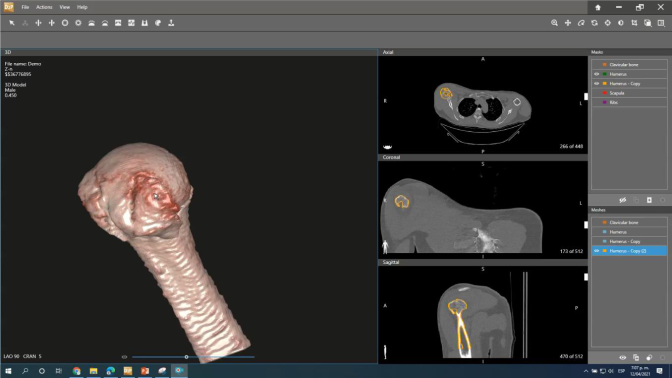

Diseño e Impresión 3D: Desarrollar soluciones impresas para los proyectos que necesiten algún tipo de prototipo o modelo funcional ya sea mecánico, anatómico o de estudio, que sean parte esencial de los proyectos de investigación. Contamos con la herramienta D2P "Dicom to Print" que permite crear modelos digitales 3D con calidad de diagnóstico e impresiones físicas 3D de forma rápida y fácil